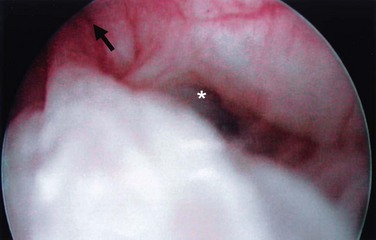

Cystourethroscopy is performed both in an attempt to visualize the UD ostium as well as to rule out other causes for the patient’s LUTS. A flexible fiberoptic cystoscope or specially designed rigid female cystoscope can be extremely helpful in evaluating the female urethra. The short beak of the female cystoscope and the lack of a beak on a flexible cystoscope maintains the discharge of the irrigation solution immediately adjacent to the lens and thus aids in distention of the relatively short (as compared to the male) urethra, permitting improved visualization. It may also be advantageous to compress the bladder neck while simultaneously applying pressure to the diverticular sac with an assistant’s finger. Luminal discharge of purulent material can often be seen with this maneuver or with simple digital compression of the UD during urethroscopy. The UD ostium is most often located posterolaterally at the level of the midurethra but can be very difficult to identify in some patients (Fig. 78–18). The success in identifying a diverticular ostium on cystourethroscopy is highly variable and is reported to be 15% to 89% (Davis and Robinson, 1970; Leach and Bavendam, 1987; Ganabathi et al, 1994). As a note of caution, patients with UD are often highly symptomatic, and endoscopic examination can be very difficult to initiate or complete without anesthesia. Notably, a positive exam may help in surgical planning; however, the failure to locate an ostium on cystourethroscopy should not influence the decision to proceed with further investigations or surgical repair.